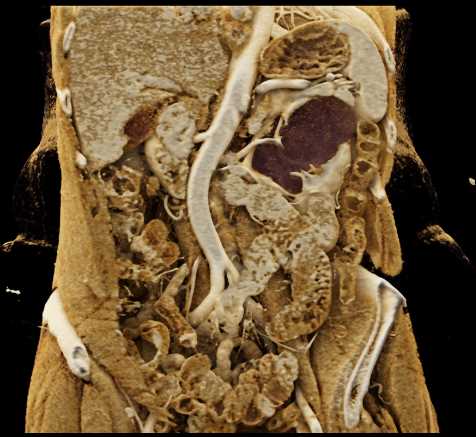

Transitional Cell Carcinoma Left Kidney